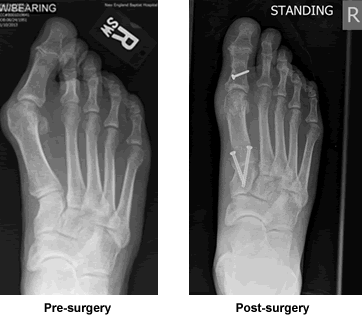

His advice was right on and absolutely correct. I have now fully recovered from his excellent surgery, my foot looks normal for the first time in 50 years, and I have started a rehab program. I have been extremely happy with Dr. Leavitt's approach to my problem, his surgical expertise, his post-operative care, and most importantly, his realistic advice throughout.